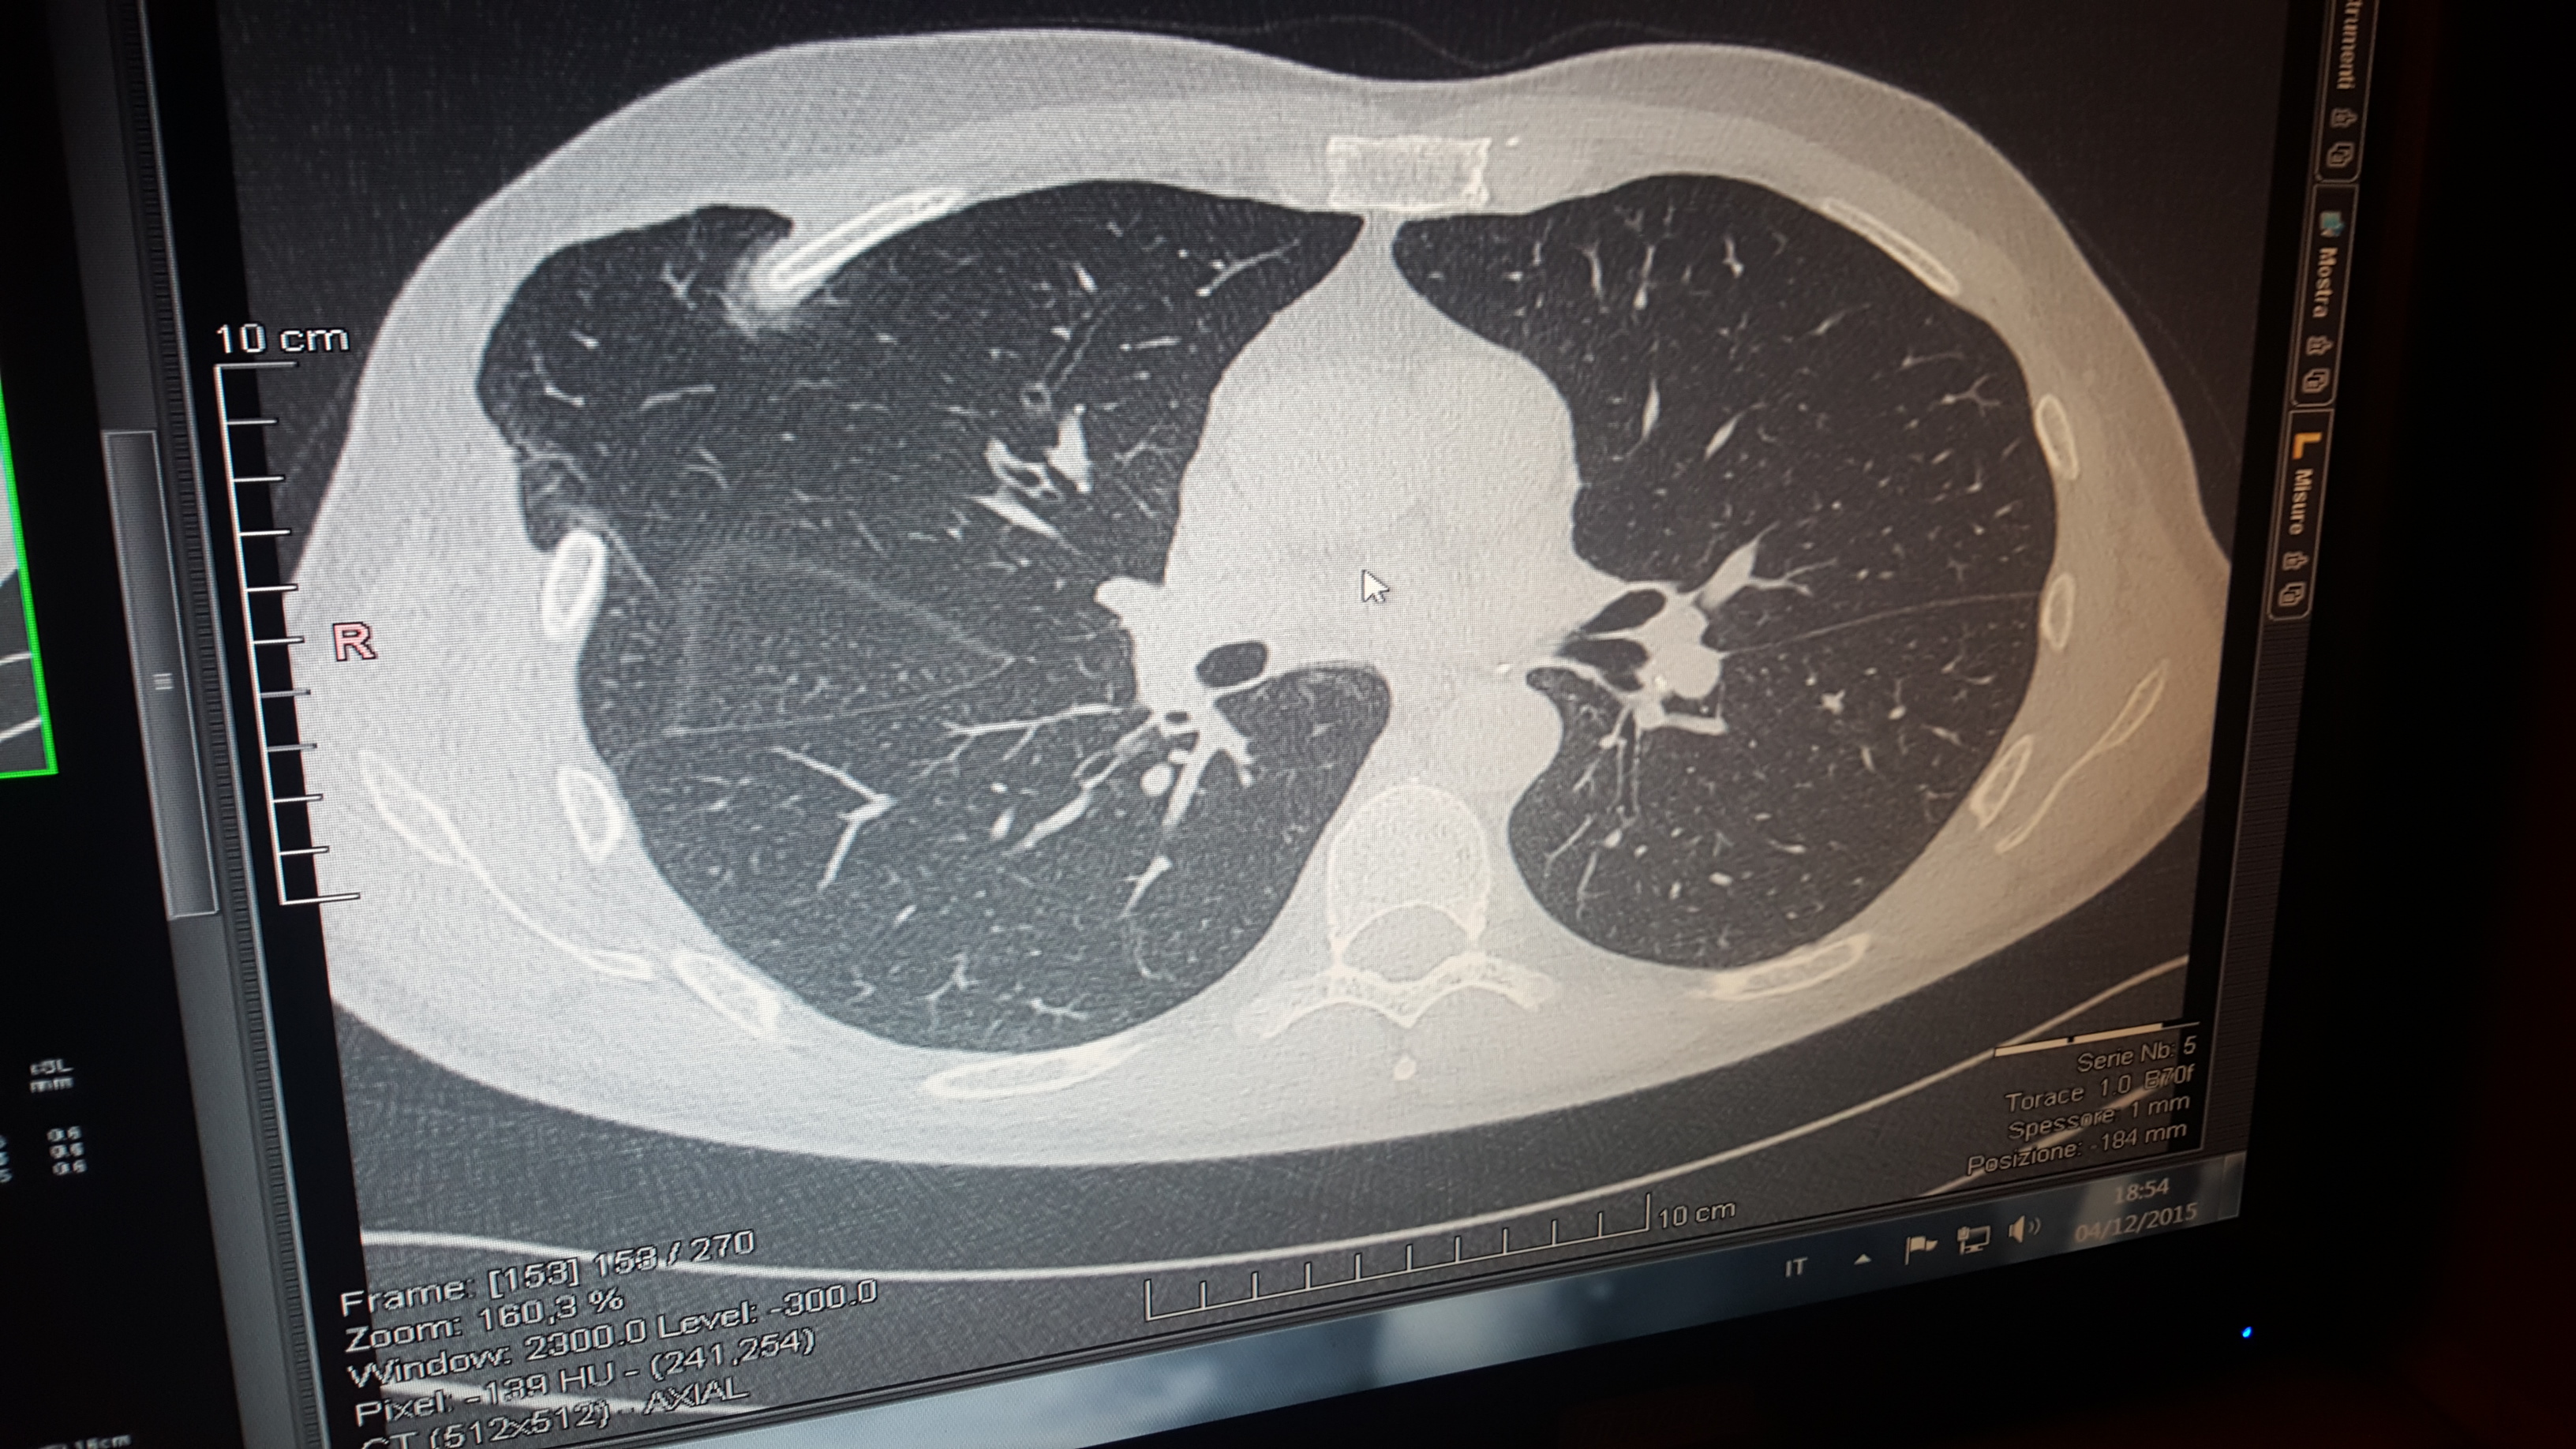

Gentile Dottore, sono Davide Riso di 56 anni, due anni fa ho subito un'intervento in microtoracotomia dx per valvulopatia mitralica con buon esito cardiaco, ma da qualche mese ho scoperto con una TAC una vasta ernia polmonare a causa del cedimento dei punti interni. Ad ogni colpo di tosse,sforzo anche poco intenso il polmone esce e rientra dallo spazio intercostale. L'intervento riparatore mi è stato sconsigliato per la sua complessità tranne che insorgano complicazioni. Che tipo di complicazioni mi devo aspettare nel tempo?

- Allego TAC

Commento file: TAC Polmonare